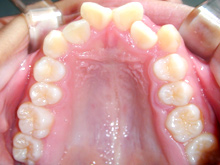

常滑市小林町在住 S.T様(15歳女性)

S.T様は下顎前歯の叢生が主訴でお母様と無料矯正相談で来院されました。

口を閉じる際に口元の緊張があり、横顔に突出感がありました。

以前に上顎前歯の部分矯正をされたご経験があるとお話しされておりました。

そのためか上顎犬歯の横幅(幅径)が通常より少なく思いました。

試料採取より診断の結果、上顎の前歯にも軽度の叢生があり、口元の緊張を改善し、

前歯の叢生の治療のために抜歯が必要であることを説明し、了承が得られたので本格矯正で治療をすすめることとなりました。

上顎前歯に軽度の叢生、下顎前歯に叢生がみられます前歯の上下の接触状態が緊密でなく軽度の舌癖の存在を疑います。

臼歯部は1歯 対 2歯で咬んでいます。